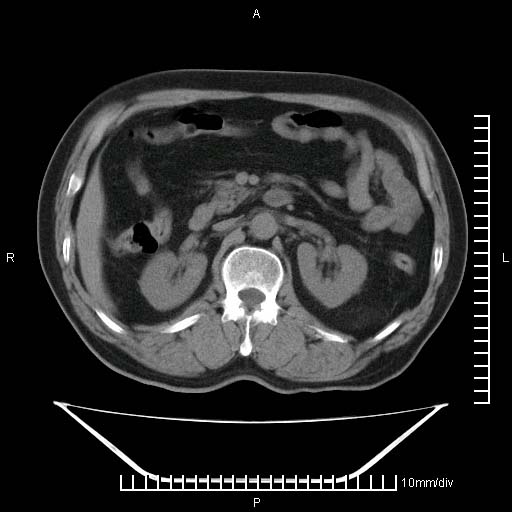

标题: CT25082:肝脏增强:男性,70岁 [打印本页]

标题: CT25082:肝脏增强:男性,70岁

患者以心脏疾病收住院,腹部无明显症状,b超查肝脏有占位。

牛眼征,中心坏死无强化,外缘强化,最外缘又见低密度,考虑转移,与脓肿鉴别

肝内多发转移瘤,右下肺炎症并少量胸水。胃壁增厚建议胃镜,胰尾部“病变”为肠管。

1)肝脏多发性转移瘤(不排除胰尾癌转移所致可能)。2)腹水。3)右侧少量胸腔积液。

胰尾占位?结肠脾曲?

ct25082 结果:转移瘤

外院mr结果:胰尾恶性占位。

肝多发低密度灶;轻度强化,较水密度高,考虑转移,不排除肝脓肿